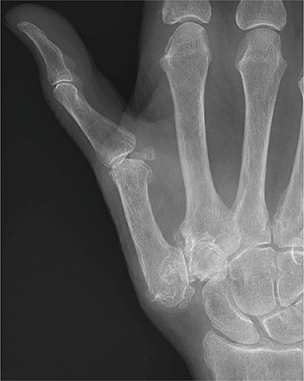

Kennistoets Duimbasisartrose

1. CMC-I-artrose geeft aanvankelijk pijnklachten bij de duimbasis. In latere stadia kan er sprake zijn van (kortdurende) ochtendstijfheid en nachtelijke pijn. Welke functiebeperking(en) kunnen optreden in het beloop van deze aandoening?

3. Anamnese en lichamelijk onderzoek dragen bij aan de diagnostiek van CMC-I-artrose. Bij het lichamelijk onderzoek is palpatie van de gewrichtsspleet pijnlijk. Welk onderzoek adviseert Broekman nog meer om CMC-I-artrose aan te tonen?

4. Artrose in de hand is vooral gelokaliseerd in het CMC-1-gewricht en de PIP- en DIP-gewrichten. Reumatoïde artritis heeft een voorkeur voor het polsgewricht. Wat zijn nog meer karakteristieke locaties van reumatoïde artritis in de hand?